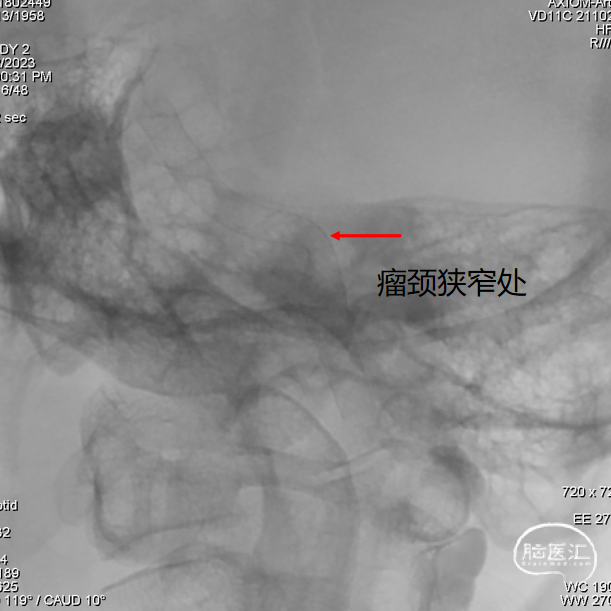

② 瘤颈处血管稍狭窄,可能影响支架展开和贴壁效果;

由于瘤颈处稍狭窄,支架通过后影响后半段支架的打开,通过“推拉结合” 的方式顺利将后半段支架打开,提示支架优秀的展开能力。